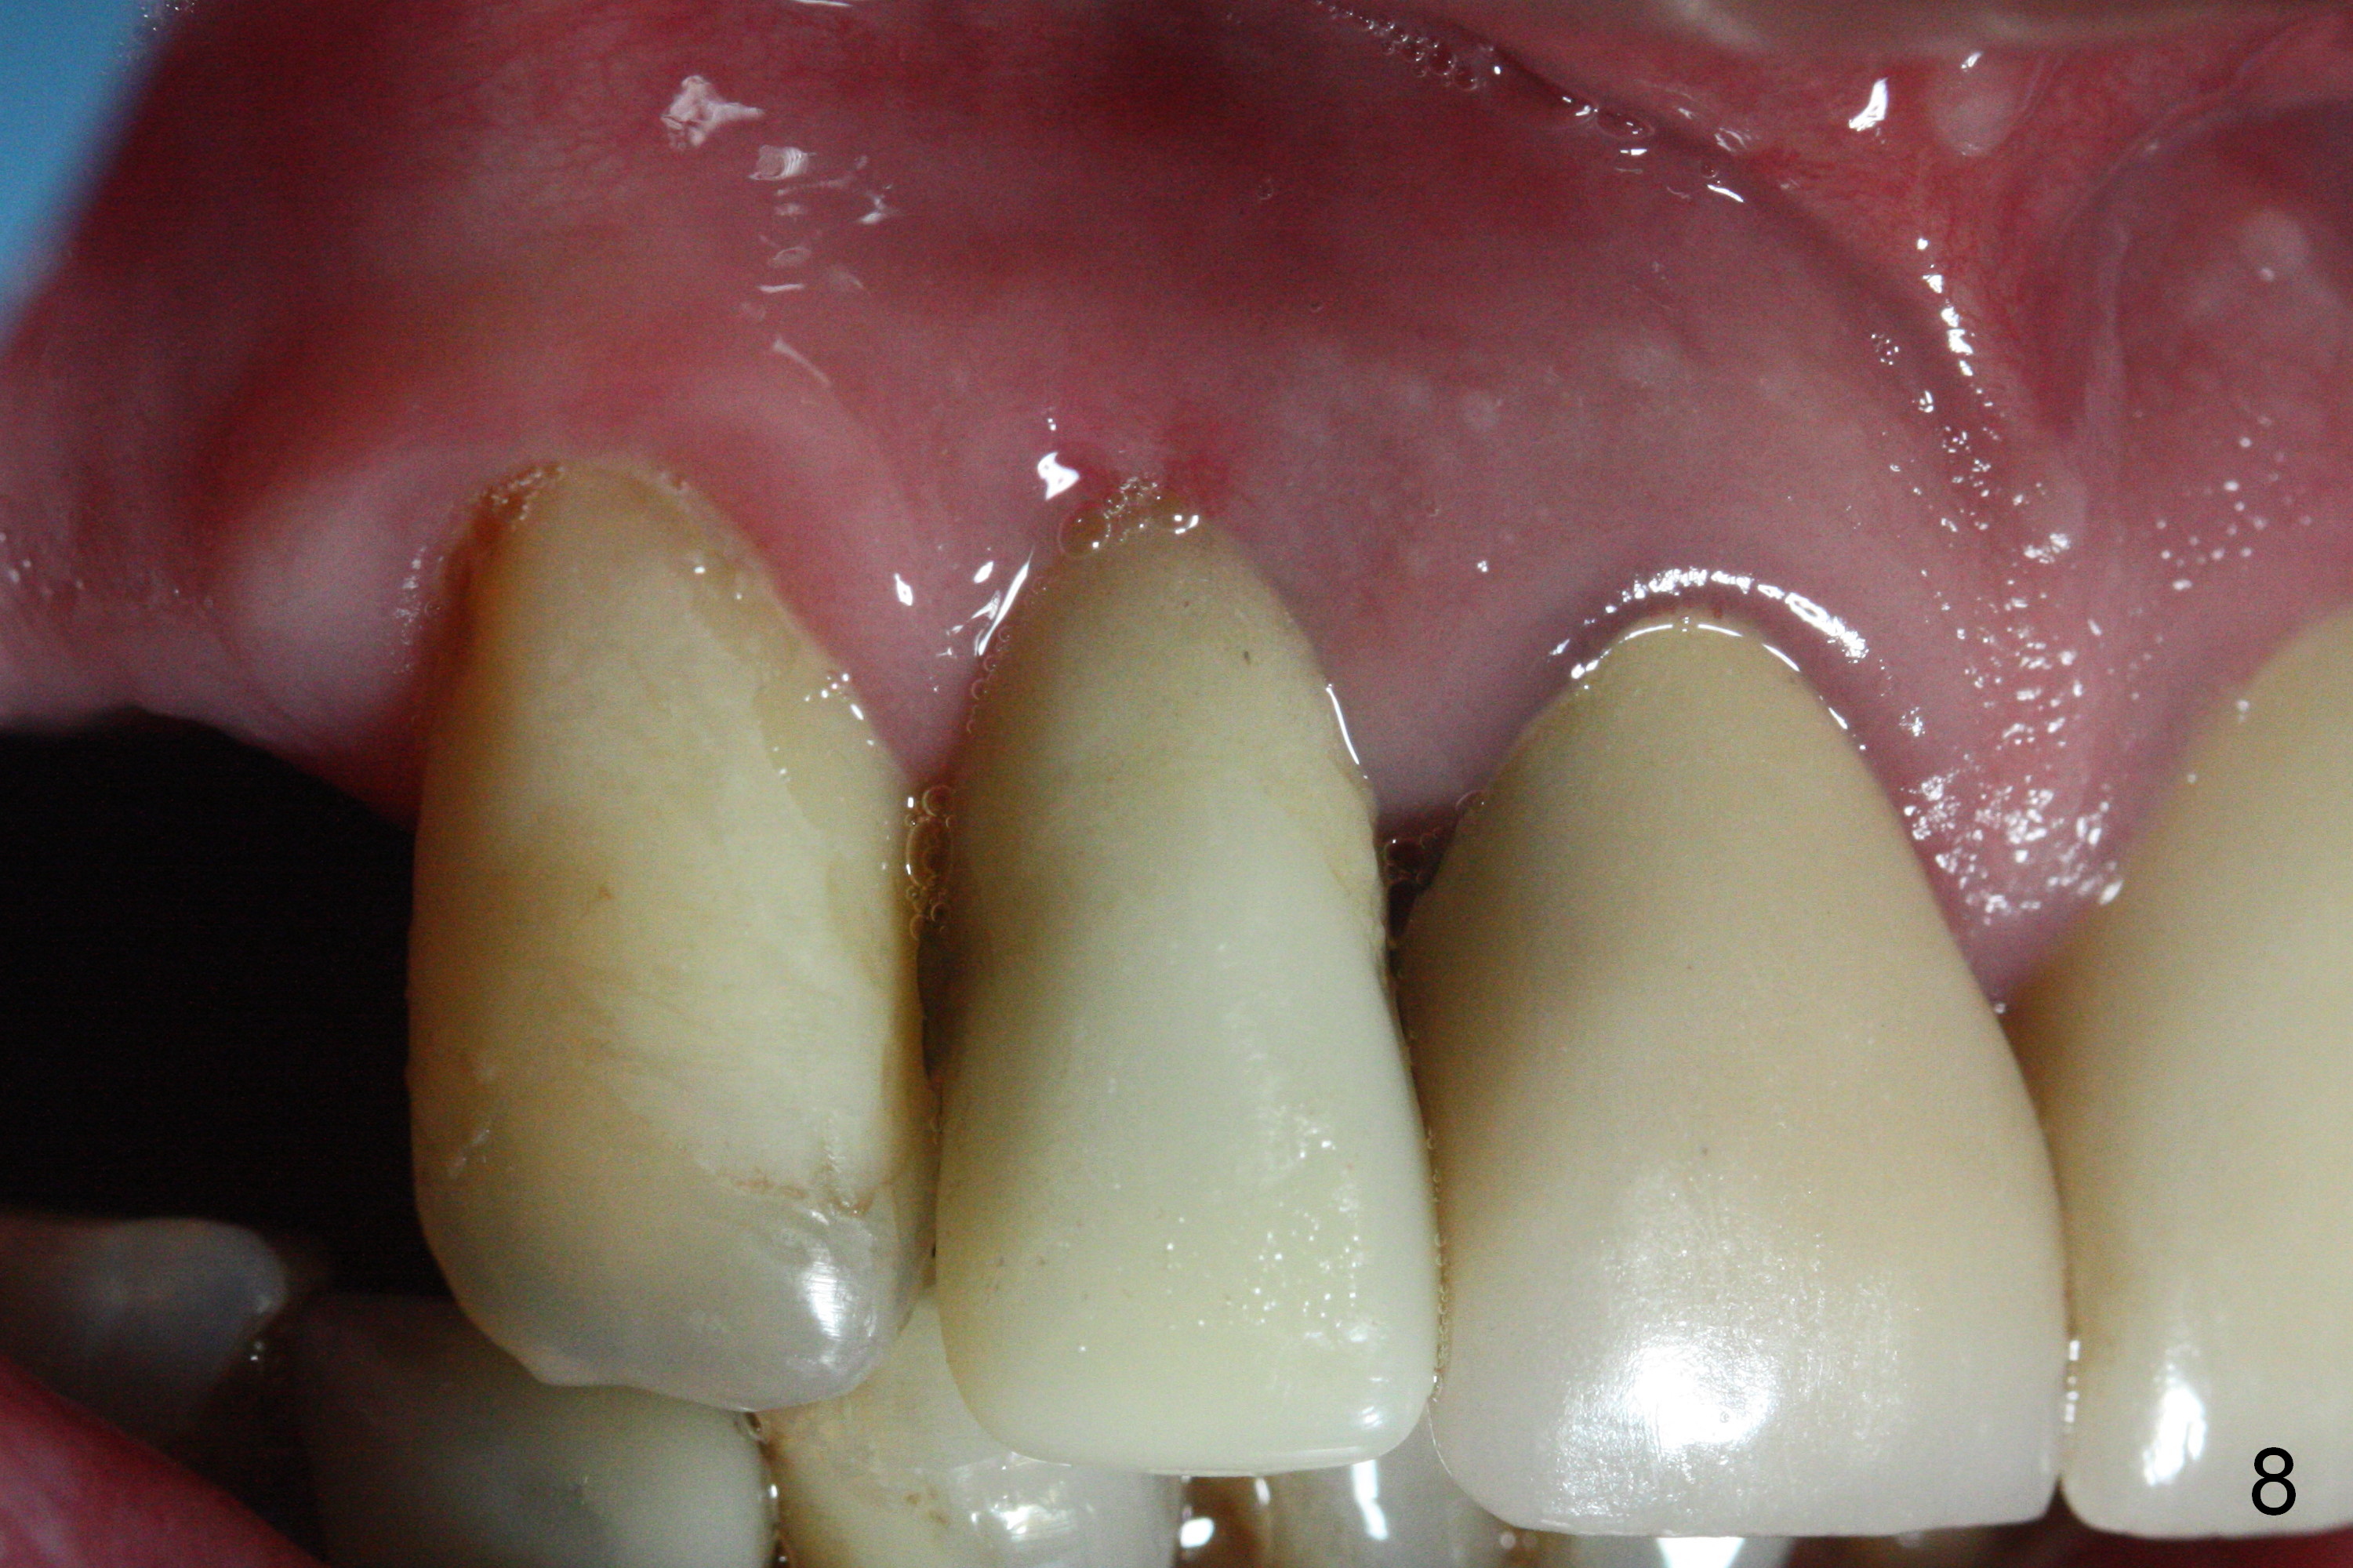

The gingiva adapts well to the provisional 1 week postop (Fig.8). The buccal gingiva remains recessive and the buccal plate is concave 5.5 months postop (Fig.9-11). It appears that the coronal portion of the buccal plate is resorbed 12 months postop (6 months post cementation, Fig.12 >). Socket shield or smaller diameter implant should have been done to avoid bone loss. Reanalysis of CBCT reveals that implantation apparently increases the bone width and that the buccal plate resorption is not so severe (Fig.13,14 (>: coronal end of the buccal plate)). Panoramic X-ray is taken 2 year 5 month post cementation.